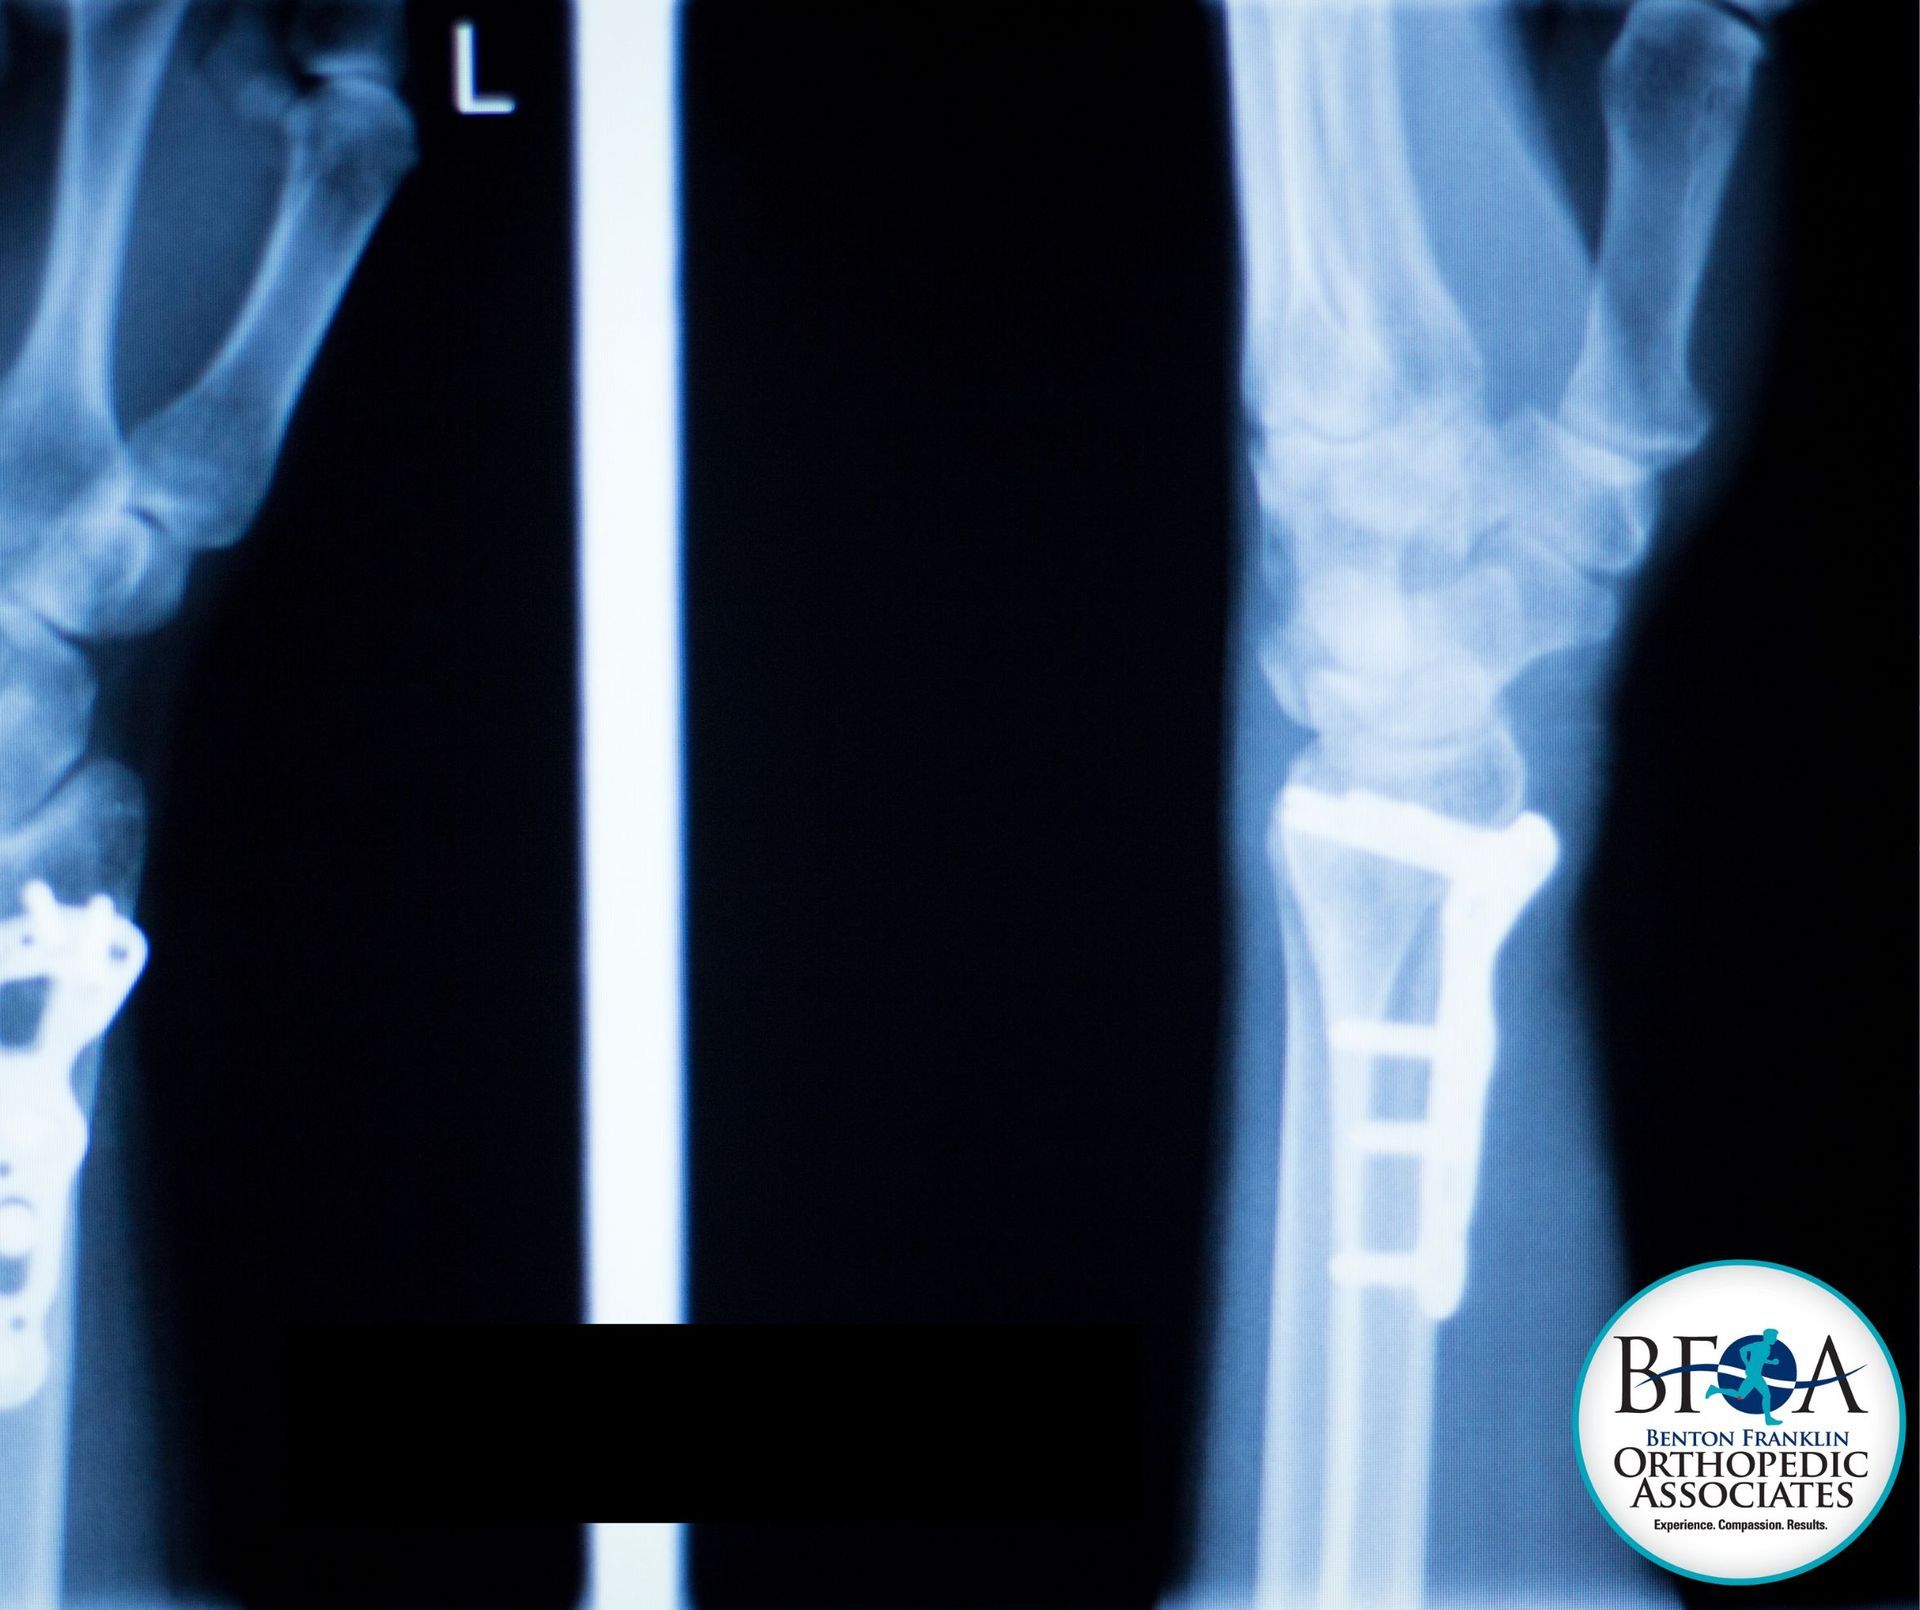

Ulnar shortening osteotomy is a precise surgical procedure that involves removing a small section of the ulna and stabilizing the bone with a plate and screws.

- Ulnar impaction syndrome confirmed by imaging